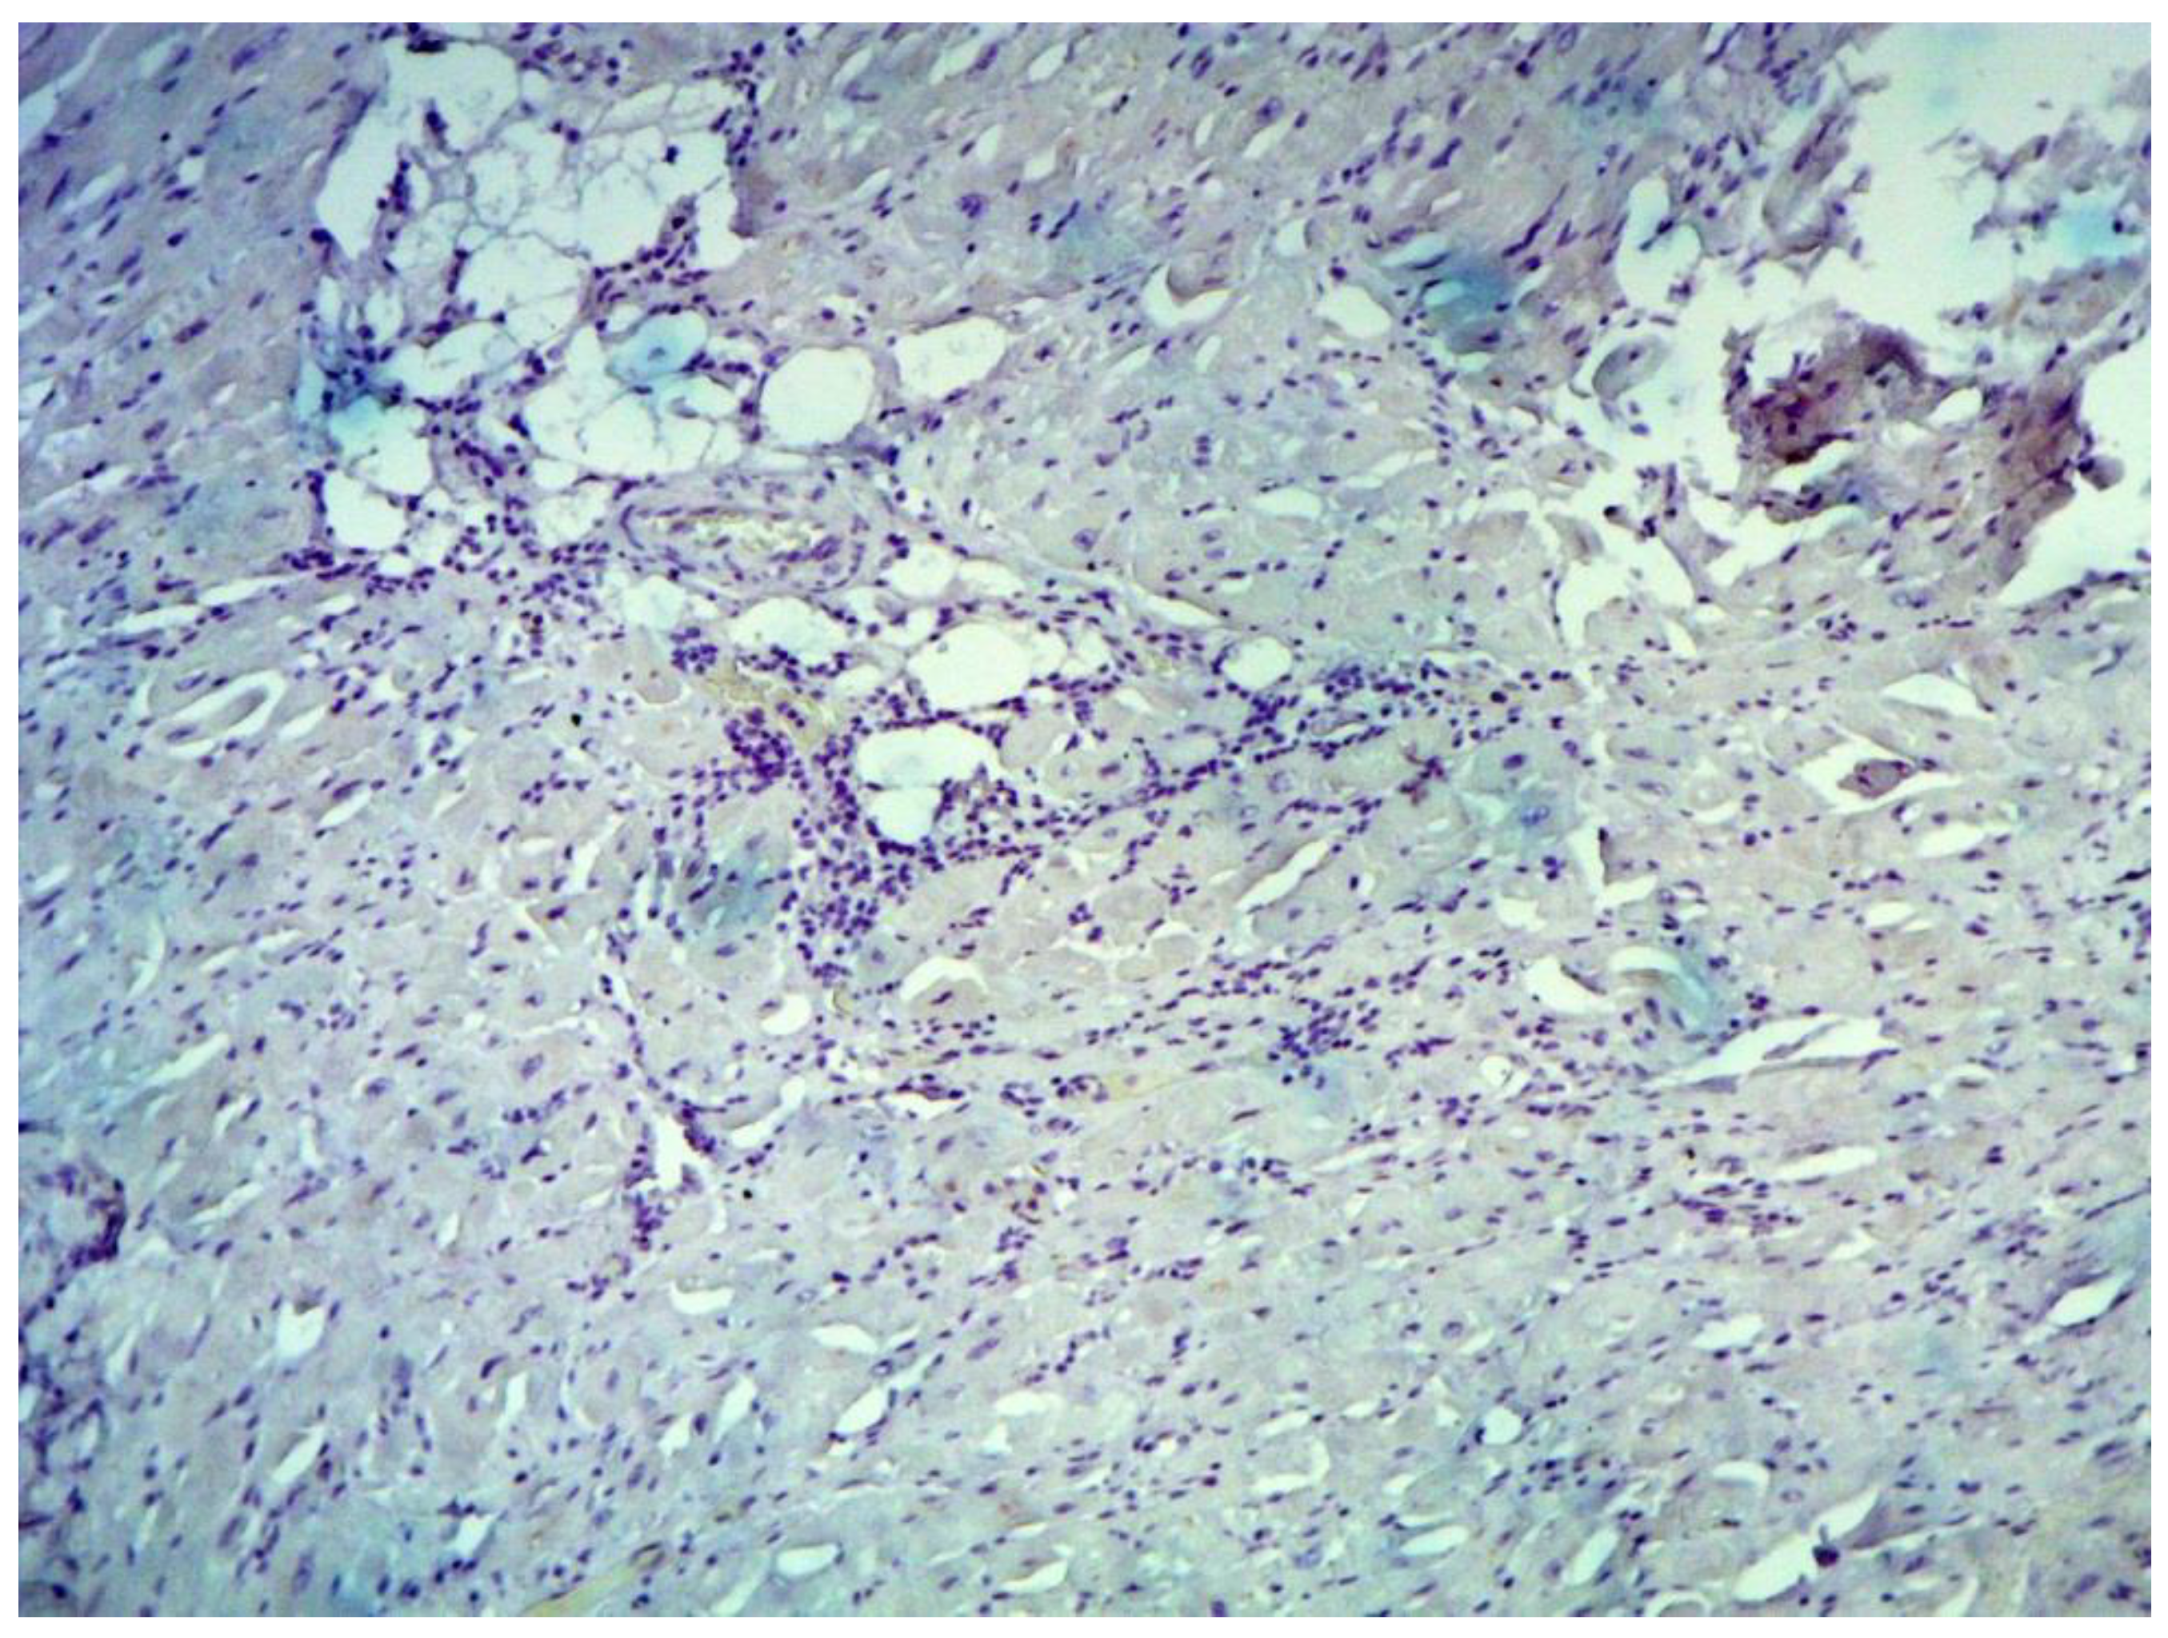

According to the Dallas criteria, the presence of histological myocarditis was revealed in 23 patients (34.3%) (Figure 6). Moreover, the virus expression was detected in 18 of these patients (78.3%), according to the results of immunohistochemical analysis. One patient (5.6%) was found to express three viruses: enterovirus, human herpes simplex virus type 1, and Epstein-Barr virus; six patients (33.3%) had the presence of two viruses: one patient had a combination of parvovirus and herpes simplex virus type 2; three patients had a combination of enterovirus and herpes simplex virus type 1; and two patients had a combination of Epstein-Barr virus and human herpes simplex virus type 2. The presence of one viral antigen was detected in 11 cases (61.1%), including five patients (27.8%) with Epstein-Barr virus, three patients (16.7%) with enterovirus (Figure 7), two patients (11.1%) with human herpes simplex virus, and one patient (5.6%) with parvovirus. Another five patients (21.7%) did not have viral infection.

Figure 6. Active lymphocytic histological myocarditis, ×100. Hematoxylin-Eosin staining.

Jcm 12 01254 g006